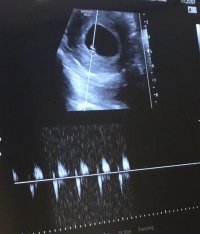

5 haftalıkken sağda üst köşede gözükmüştü. Ama Yeni gittm 7 haftalık olduk. karın ultrason görüntüleri bunlar rica etsem cinsiyet tahmininde bulunur musunuz? bu arada soldan yumurtlamışım

Ekli dosyalar

• D6A874AD-9FCB-405A-8B75-9CF3E5174581.jpeg

D6A874AD-9FCB-405A-8B75-9CF3E5174581.jpeg

169,4 KB · Görüntüleme: 209

• C2637F0F-CA8A-4868-8C21-156B562D137C.jpeg

C2637F0F-CA8A-4868-8C21-156B562D137C.jpeg

109,9 KB · Görüntüleme: 224

• 79659AC2-9C38-4FF8-8BEA-1421B734267C.jpeg

79659AC2-9C38-4FF8-8BEA-1421B734267C.jpeg

238,5 KB · Görüntüleme: 211